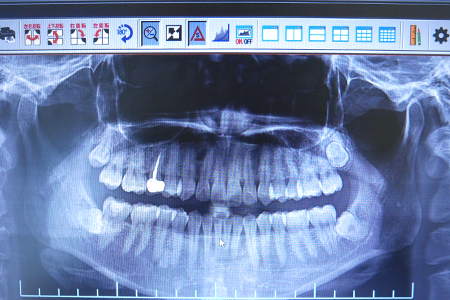

●デジタルレントゲン

当院では先進のデジタルレントゲンを導入し、従来のレントゲン撮影に比べて被ばく量を約1/10に抑えております。フィルム現像がないので、従来よりも画像を早く確認していただけます。